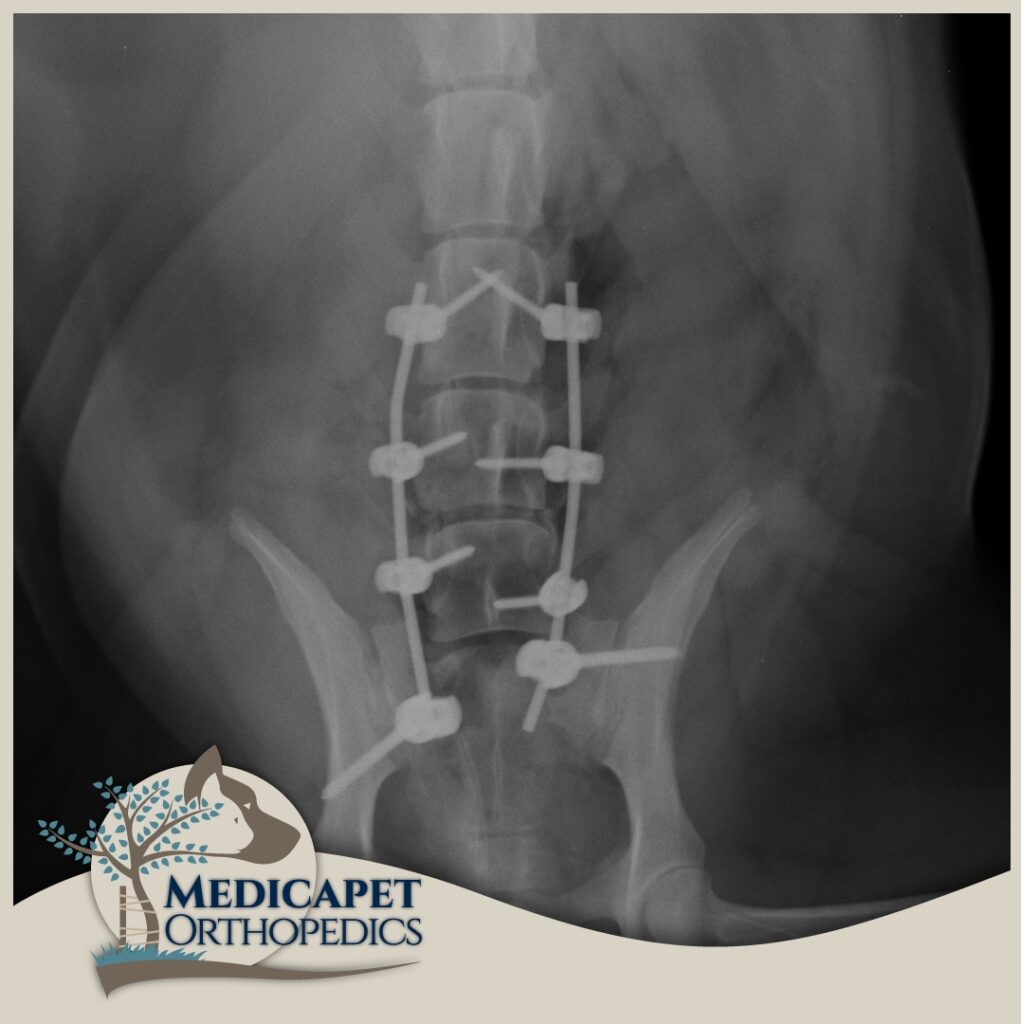

omurga cerrahisi

omurga kırıkları, disk fıtığı gibi olgularda acil müdahale başarı şansını yüksetir.

zaman geçtikçe kalıcı felç olasılığı artar.

zaman geçirmeden bize ulaşın

Kliniğimizde karşımıza çıkan sinir sistemi hasarlı hastaların pek çoğu bu hasarı bazı kazalar

sonucunda almış olarak geliyorlar. Trafik kazaları, yüksekten düşmeler, insan saldırısı, başka bir

hayvanın saldırısı gibi olayların sonucunda özellikle omurgada kırıklar, kırık bulunmayan omurga

travmaları, kafatası hasarları, kol – bacak ve kalça kırıklarına bağlı geçici ya da kalıcı felç durumları

gibi durumlar en sık tedavi ve opere ettiklerimizin başında geliyor. Öte yandan bazı ırkların genetik

yatkınlıkları da omurga problemlerine yol açabiliyor.